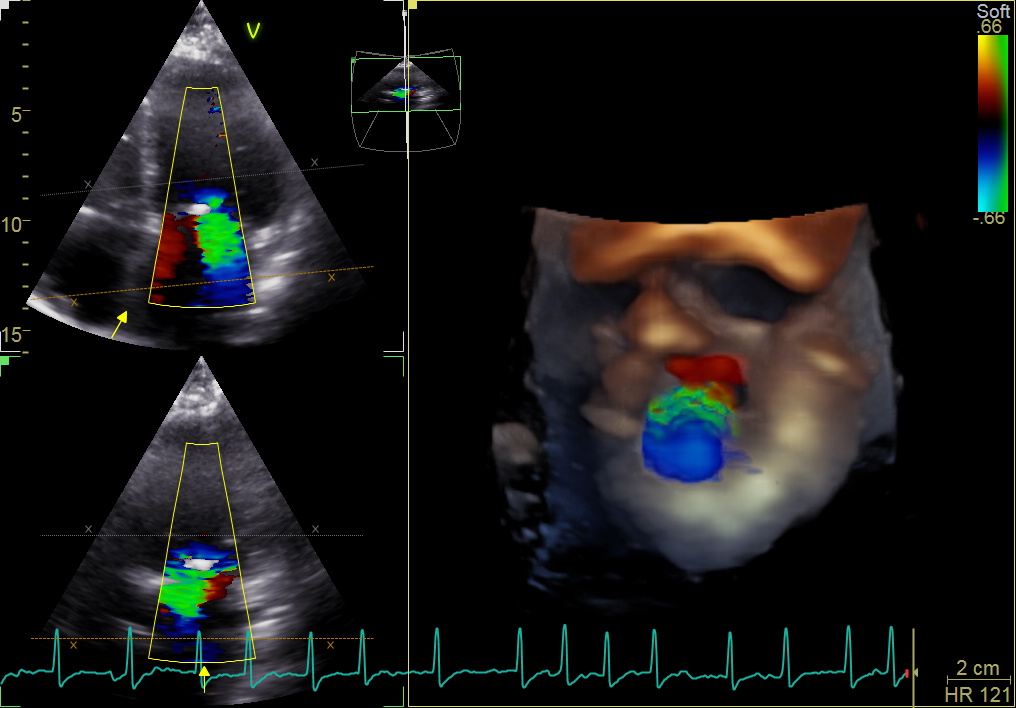

În acest moment, cea mai perfomantă și avansată ecografie la inimă este ecocardiografia 4D, care se bazează pe tehnologii ce folosesc inteligența artificială.

Ecografia 4D, pentru cea mai precisă analiză

La Centrul Medical Speranța, medicii cardiologi dr. Radu Popa şi dr. Adrian Coandă folosesc cel mai avansat echipament din România pentru efectuarea unei ecocardiografii transtoracice, atât standard, 2D, cât și în 3 sau 4 dimensiuni, comparabilă cu o ecografie făcută în cele mai avansate centre medicale din Europa.

Printre avantajele ecografiei 4D se numără analiza precisă a dimensiunilor, a formei și a altor caracteristici ale cheagurilor de sânge posibile din interiorul camerelor inimii.